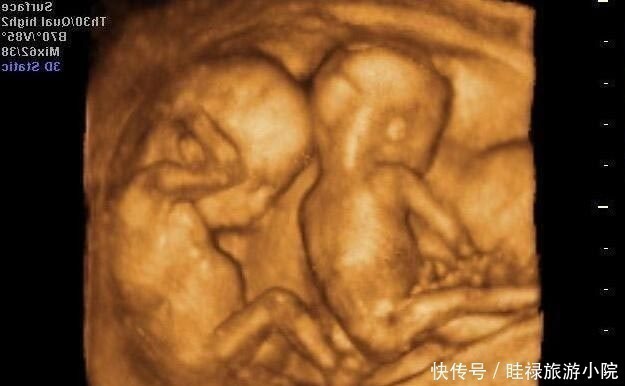

医生|孕期产检不想生个“傻孩子”,这三项产检必须按时做,不能忽视( 二 )

- 四维彩超|孕期最关键的4次产检,就算再忙,宝爸也要陪孕妈一起